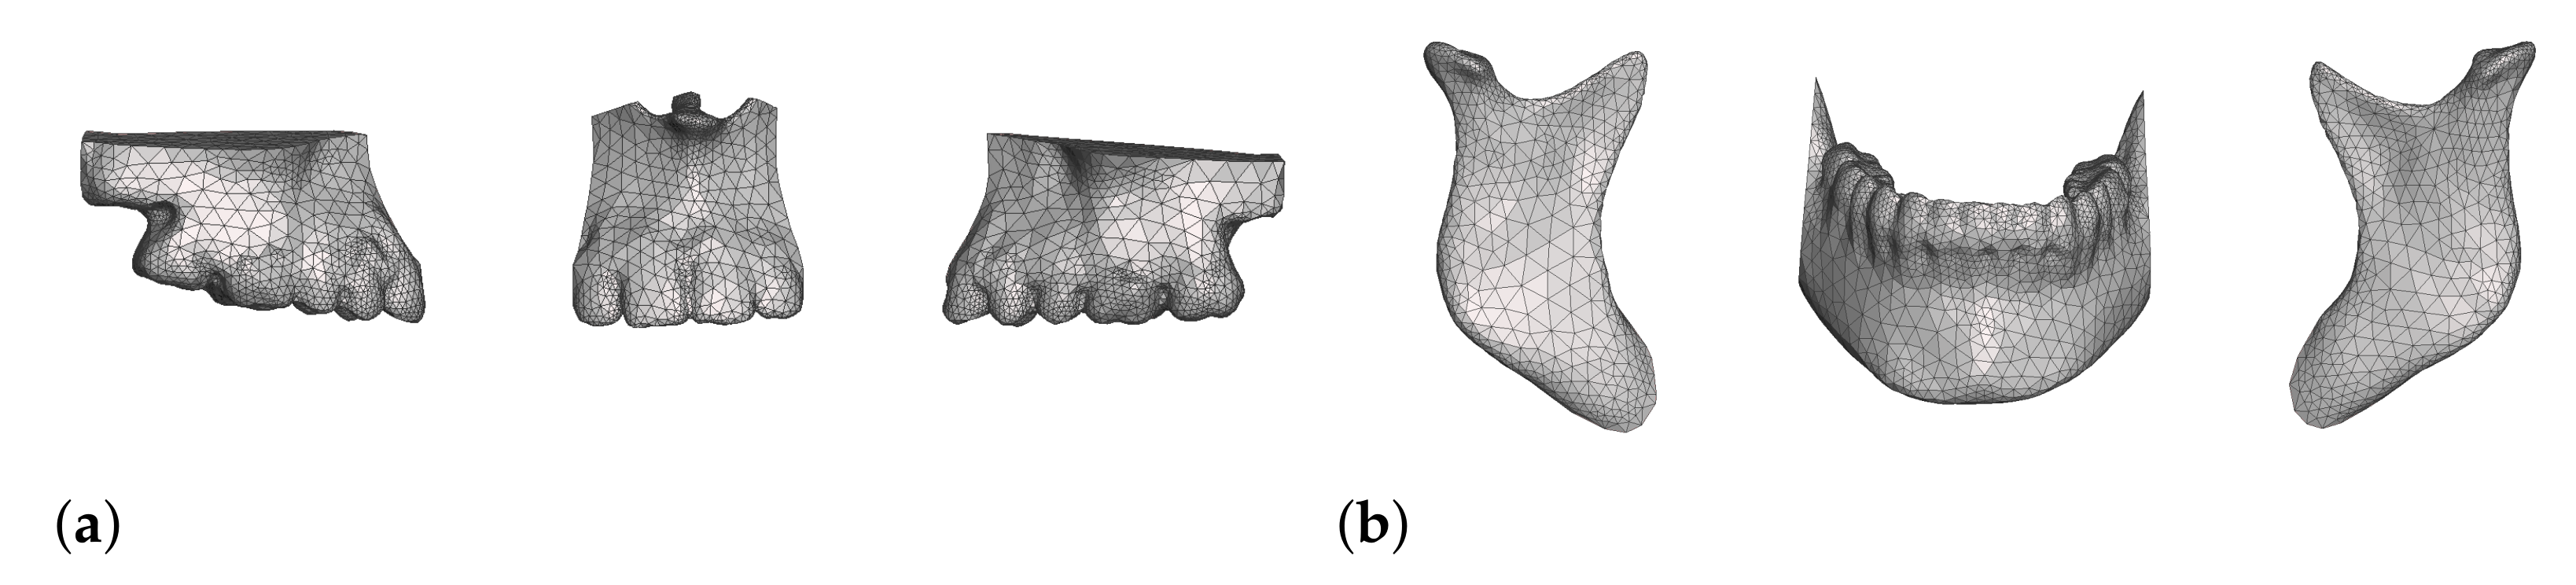

2.5. Preparation of Simulation Meshes and Couplings

2.5.1. Bones

- In maxillary procedures, the maxilla is separated from the skull through a Lefort osteotomy, classified based on its anatomical level. In this cohort, the distribution of cases is: 8 Lefort I cases and 1 Lefort II case; one patient did not undergo maxillary surgery. Moreover, after a Lefort I osteotomy, the maxilla may be segmented (typically into three fragments) in order to expand the upper arch. Maxilla segmentation was applied to 6 patients in this cohort.

- In mandibular procedures, the mandible may be sagittally split on both rami (bilateral sagittal split osteotomy, BSSO) or only one ramus (unilateral sagittal split osteotomy, USSO). In this cohort, the distribution of cases is: 7 BSSO cases, 1 USSO case; two patients did not undergo mandibular surgery. Additionally, a chin osteotomy or genioplasty may be also performed. Genioplasty was applied to 1 patient in this cohort.